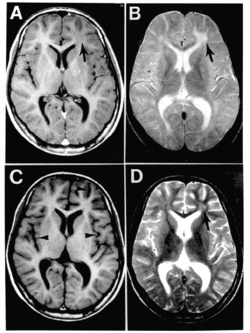

| Subacute sclerosing panencephalitis. | |

"SSPE is suspected in young patients with dementia and neuromuscular irritability. EEG, CT or MRI, CSF examination, and measles serologic testing are done. EEG shows periodic complexes with high-voltage diphasic waves occurring synchronously throughout the recording. CT or MRI may show cortical atrophy or white matter lesions. CSF examination usually reveals normal pressure, cell count, and total protein content; however, CSF globulin is almost always elevated, constituting up to 20 to 60% of CSF protein. Serum and CSF contain elevated levels of measles virus antibodies. Anti-measles IgG appears to increase as the disease progresses. If test results are inconclusive, brain biopsy may be needed."